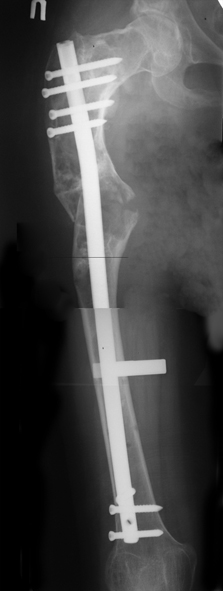

Уважаемые коллеги! С Новым годом и самых светлых пожеланий! В ноябре этого года я обращался с просьбой о помощи в выборе тактики лечения больной с деформацией бедра на почве фиброзной дисплазии. Были получены интересные и очень полезные советы по операции.

Хотелось бы показать, что получилось в результате. Операция выполнялась с помощью А.Н.Челнокова. Очень понравилась технология выполнения блокируемого остеосинтеза с использованием спицевого дистрактора, модифицированный гвоздь с латерализованным проксимальным отделом и возможностью многовинтовой фиксации проксимального и дистального участков бедра.